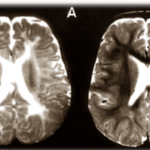

Uno studio preclinico recentemente pubblicato dai ricercatori del Lawson Health Research Institute e della Schulich School of Medicine & Dentistry della Western University suggerisce che lo svapo può avere effetti negativi sul surfattante polmonare nei polmoni. Il surfattante polmonare rappresenta un tappeto di lipidi, proteine e carboidrati che riveste gli alveoli e le vie aeree.

Il tensioattivo, uno strato critico costituito da lipidi e proteine, è essenziale per facilitare la respirazione riducendo la tensione superficiale nei polmoni. Senza tensioattivo, ci vorrebbe più sforzo per respirare e una persona avrebbe bisogno di un aiuto meccanico per farlo.